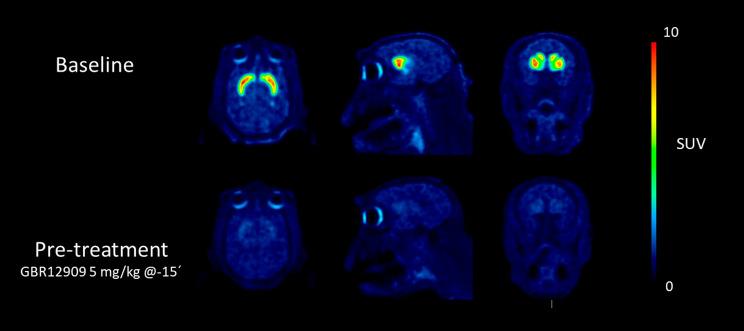

Undesired radiometabolites can be detrimental to the development of positron emission tomography (PET) radioligands. Methods for quantifying radioligand metabolites in brain tissue include ex vivo studies in small animals or labeling and imaging of the radiometabolite(s) of interest. The latter is a time- and resource-demanding process, which often includes multistep organic synthesis. We hypothesized that this process could be replaced by making use of liver microsomes, an in vitro system that mimics metabolism. In this study, rat liver microsomes were used to prepare radiometabolites of the dopamine transporter radioligand [F]FE-PE2I for in vitro imaging using autoradiography and in vivo imaging using PET in rats and nonhuman primates. The primary investigated hydroxy-metabolite [F]FE-PE2I-OH ([F]) was obtained in a 2% radiochemical yield and >99% radiochemical purity. In vitro and in vivo imaging demonstrated that [F] readily crossed the blood-brain barrier and bound specifically and reversibly to the dopamine transporter. In conclusions, the current study demonstrates the potential of liver microsomes in the production of radiometabolites for translational imaging studies and radioligand discovery.

未代谢的放射性代谢物可能会对正电子发射断层扫描(PET)放射性配体的发展产生不利影响。定量检测脑组织中放射性配体代谢物的方法包括小动物的离体研究或感兴趣的放射性代谢物的标记和成像。后者是一个耗时且资源密集型的过程,通常包括多步有机合成。我们假设可以利用肝脏微粒体(一种模拟代谢的体外系统)来替代这个过程。在这项研究中,使用大鼠肝脏微粒体来制备多巴胺转运体放射性配体[F]FE-PE2I 的放射性代谢物,用于使用放射自显影进行体外成像和使用 PET 在大鼠和非人类灵长类动物进行体内成像。主要研究的羟基代谢物[F]FE-PE2I-OH([F])的放射性化学产率为 2%,放射性化学纯度>99%。体外和体内成像研究表明,[F]很容易穿过血脑屏障,并特异性和可逆地与多巴胺转运体结合。总之,目前的研究表明肝脏微粒体在生产放射性代谢物用于转化成像研究和放射性配体发现方面具有潜力。